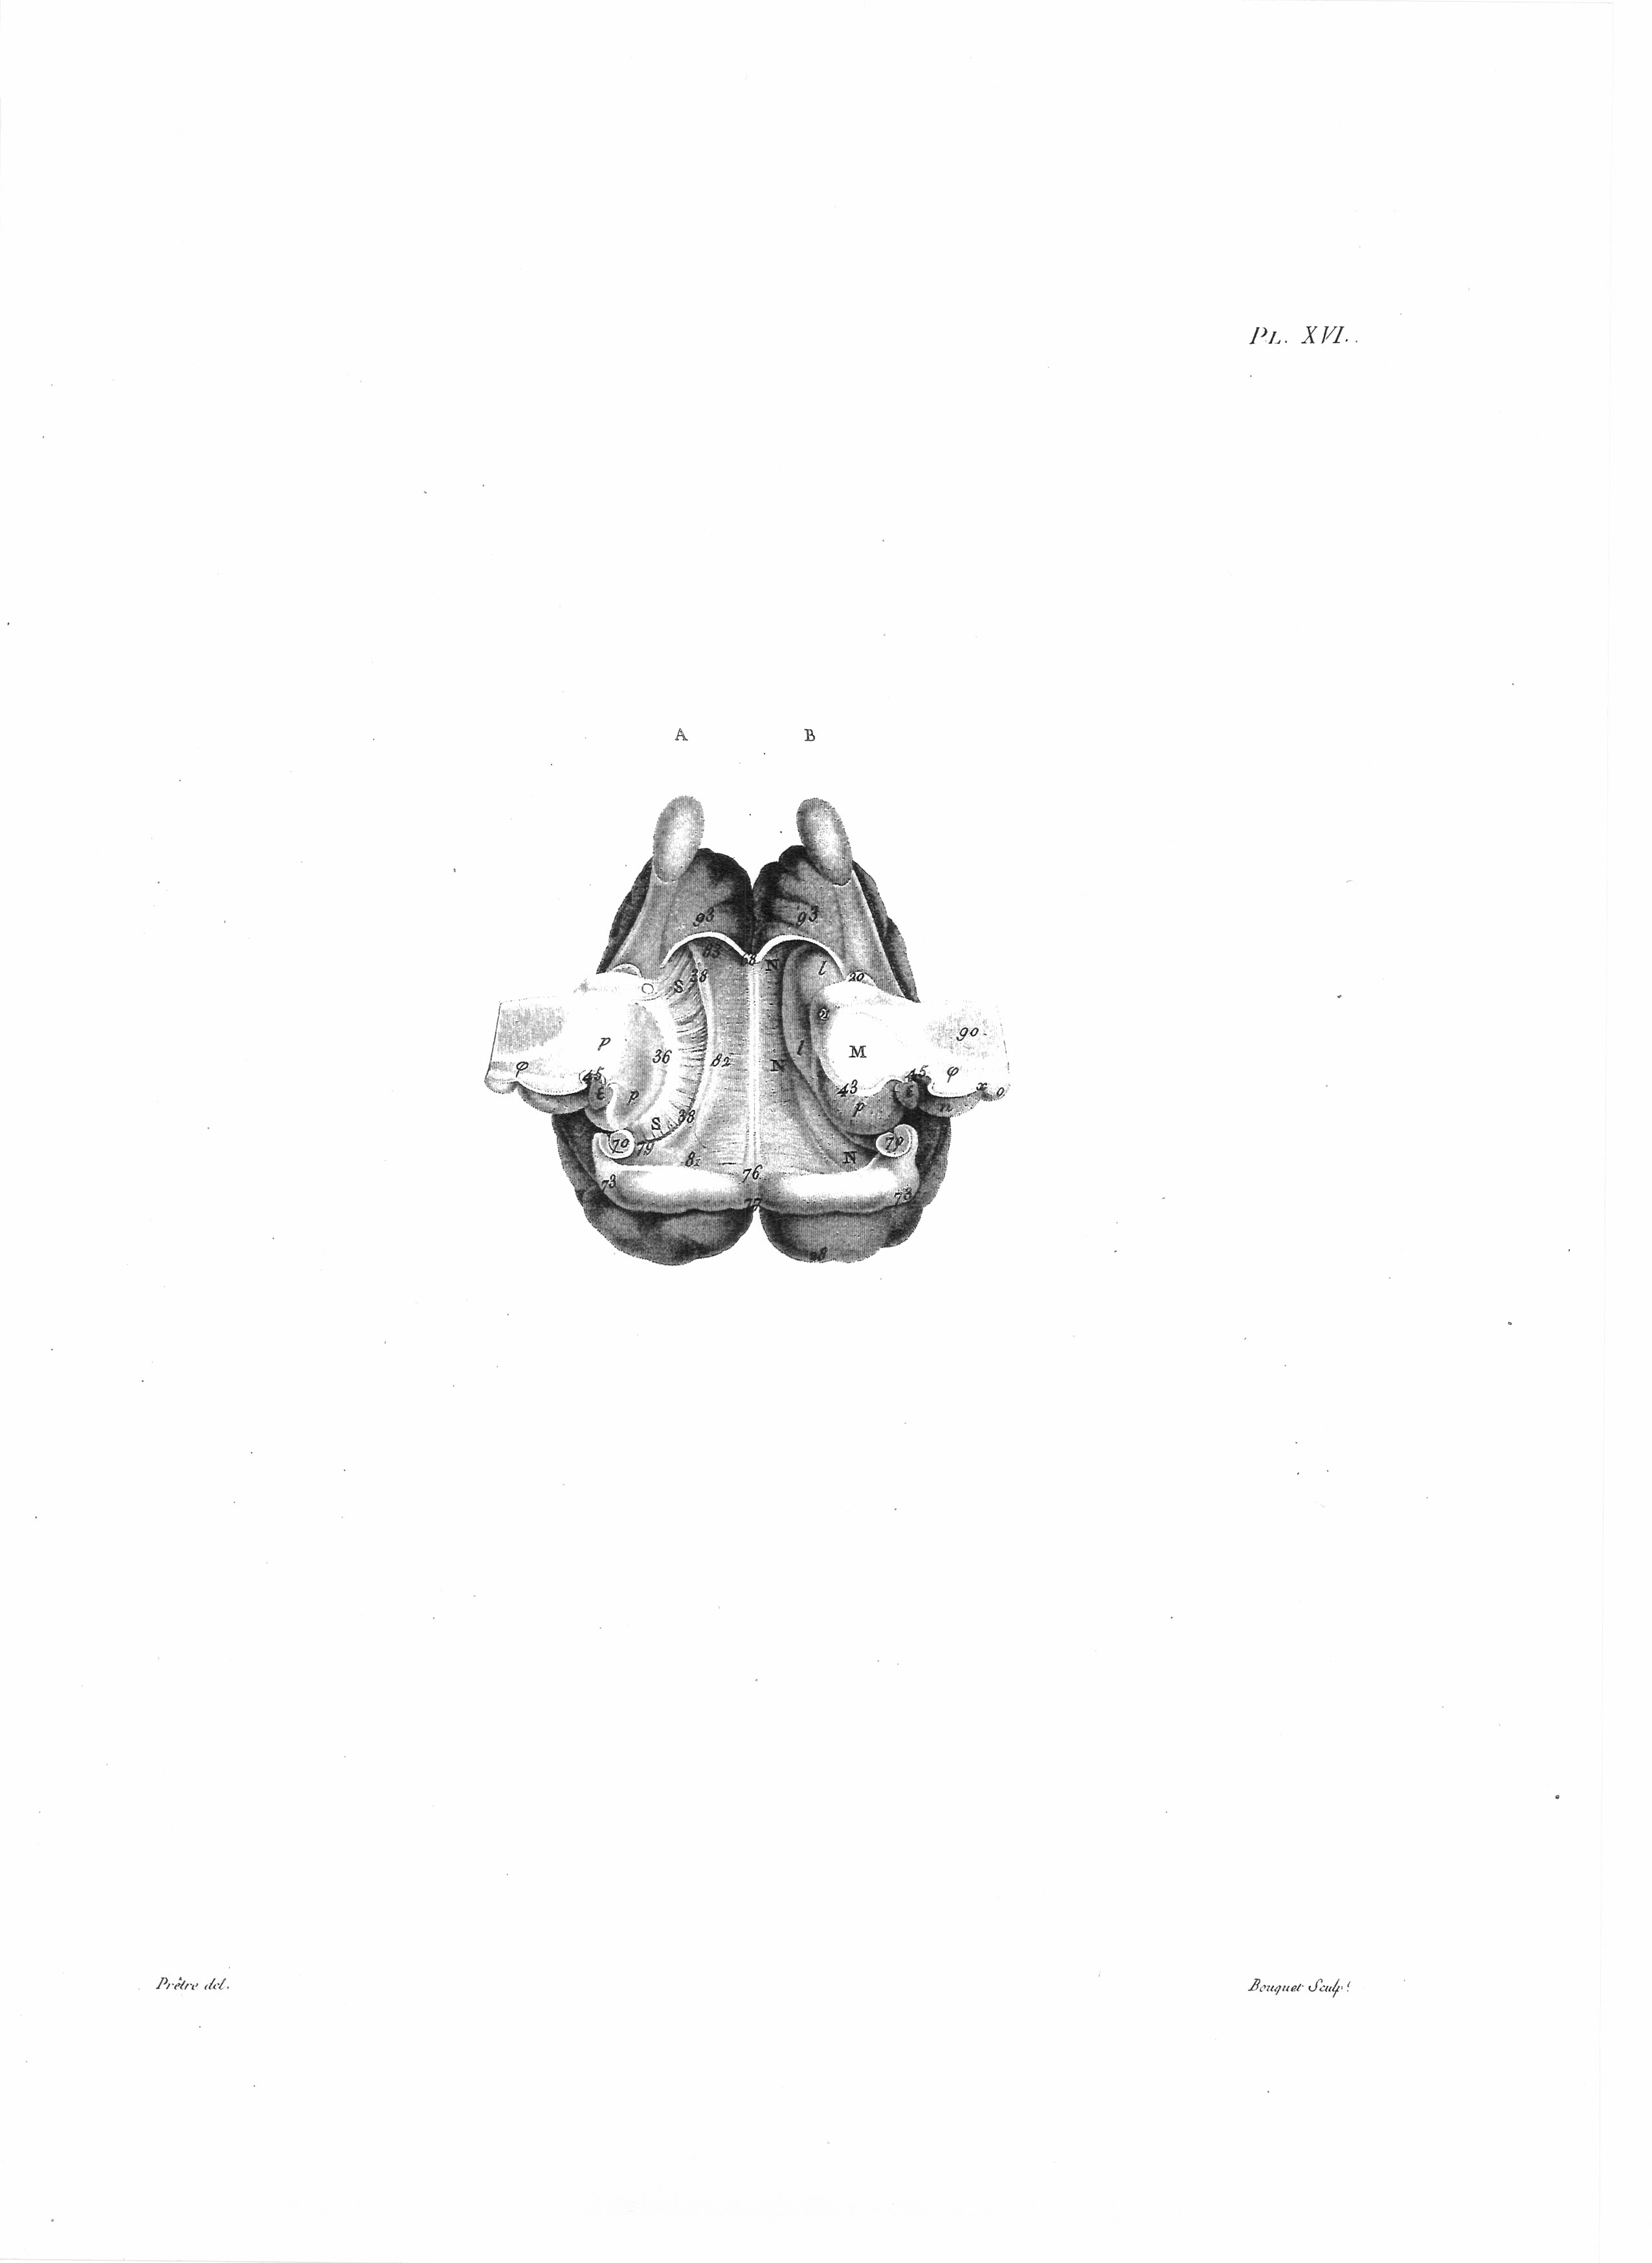

Gall, F. J. (1818). Anatomie et physiologie du système nerveux en général, et du cerveau en particulier, Avec des observations sur la possibilité de reconnoître plusieurs dispositions intellectuelles et morales de l´homme et des animaux, par la configuration de leurs têtes.

Librairie Grecque-Latine-Allemande, Vol. 3, I-XXXV u. 1-379 100 planches.